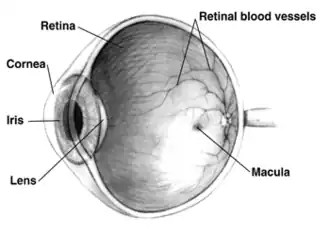

A cataract is a cloudy area in the lens of the eye that leads to a decrease in vision of the eye.[1][7] Cataracts often develop slowly and can affect one or both eyes.[1] Symptoms may include faded colours, blurry or double vision, halos around light, trouble with bright lights, and difficulty seeing at night.[1] This may result in trouble driving, reading, or recognizing faces.[8] Poor vision caused by cataracts may also result in an increased risk of falling and depression.[2] In 2020, Cataracts cause 39.6% of all cases of blindness and 28.3% of visual impairment worldwide. Cataract remains the single most common cause of global blindness.[3]

Cataracts are most commonly due to aging but may also occur due to trauma or radiation exposure, be present from birth, or occur following eye surgery for other problems.[1][4] Risk factors include diabetes, longstanding use of corticosteroid medication, smoking tobacco, prolonged exposure to sunlight, and alcohol.[1] In addition to these, poor nutrition, obesity, chronic kidney disease, and autoimmune diseases have been recognized in various studies as contributing to the development of cataracts.[9] Cataract formation is primarily driven by oxidative stress, which damages lens proteins, leading to their aggregation and the accumulation of clumps of protein or yellow-brown pigment in the lens. This reduces the transmission of light to the retina at the back of the eye, impairing vision. Additionally, alterations in the lens’s metabolic processes, including imbalances in calcium and other ions, contribute to cataract development.[10][1] Diagnosis is typically through an eye examination,[1] with ophthalmoscopy and slit-lamp examination being the most effective methods. During ophthalmoscopy, the pupil is dilated, and the red reflex is examined for any opacities in the lens. Slit-lamp examination provides further details on the characteristics, location, and extent of the cataract.[11]